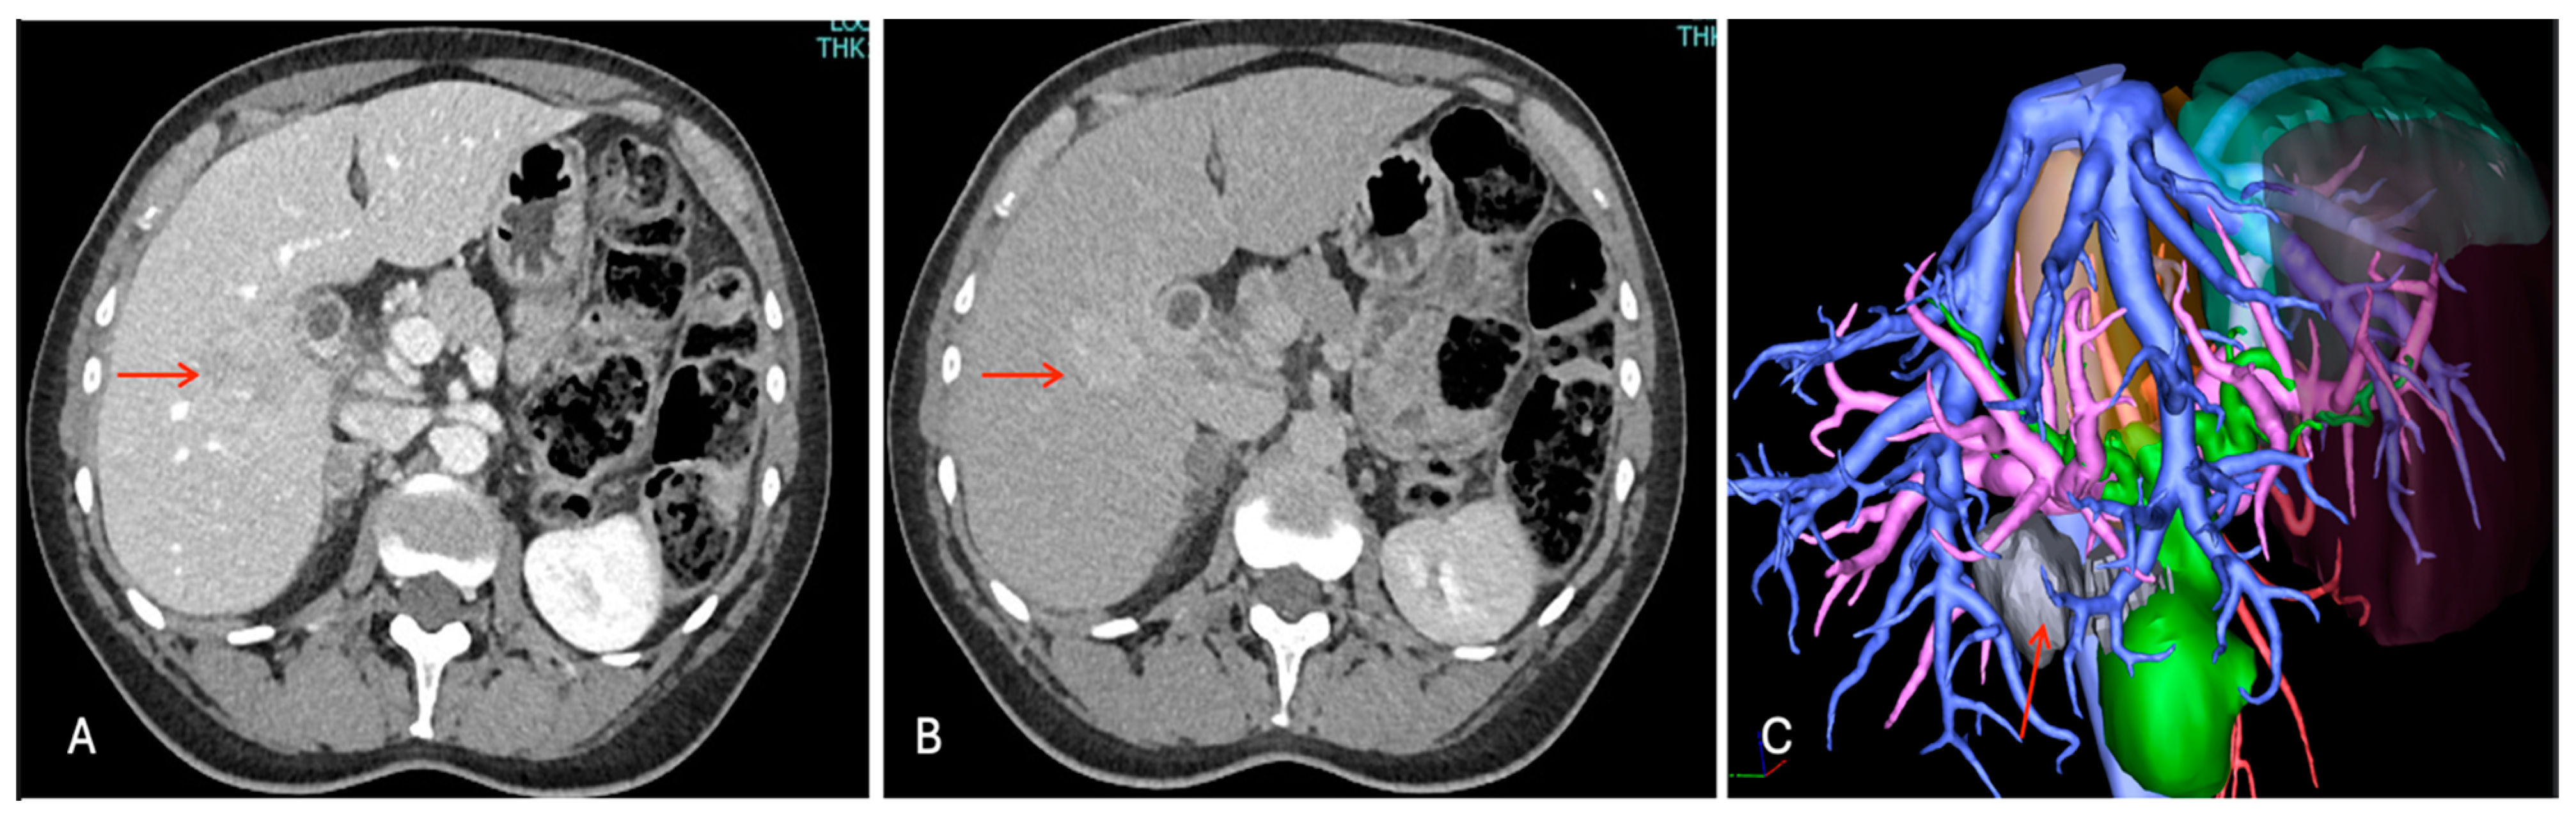

The chest and abdominal enhanced CT scan with 3D reconstructions (Figure 3) confirmed a nodule with an increasing enhancement in the portal phase, thus confirming a suspect of malignancy but without any sign of vascular infiltration, distant metastases, and/or associated lymphadenopathy or cirrhosis.

Figure 3.

Contrast enhancement CT images with 3D reconstruction. Liver mass in segment 5 (red arrow), (A) iso-slightly hyperdensity in arterial phase, (B) progressive enhancing in portal phase, and (C) 3D reconstruction with relationship between tumor and vessels.